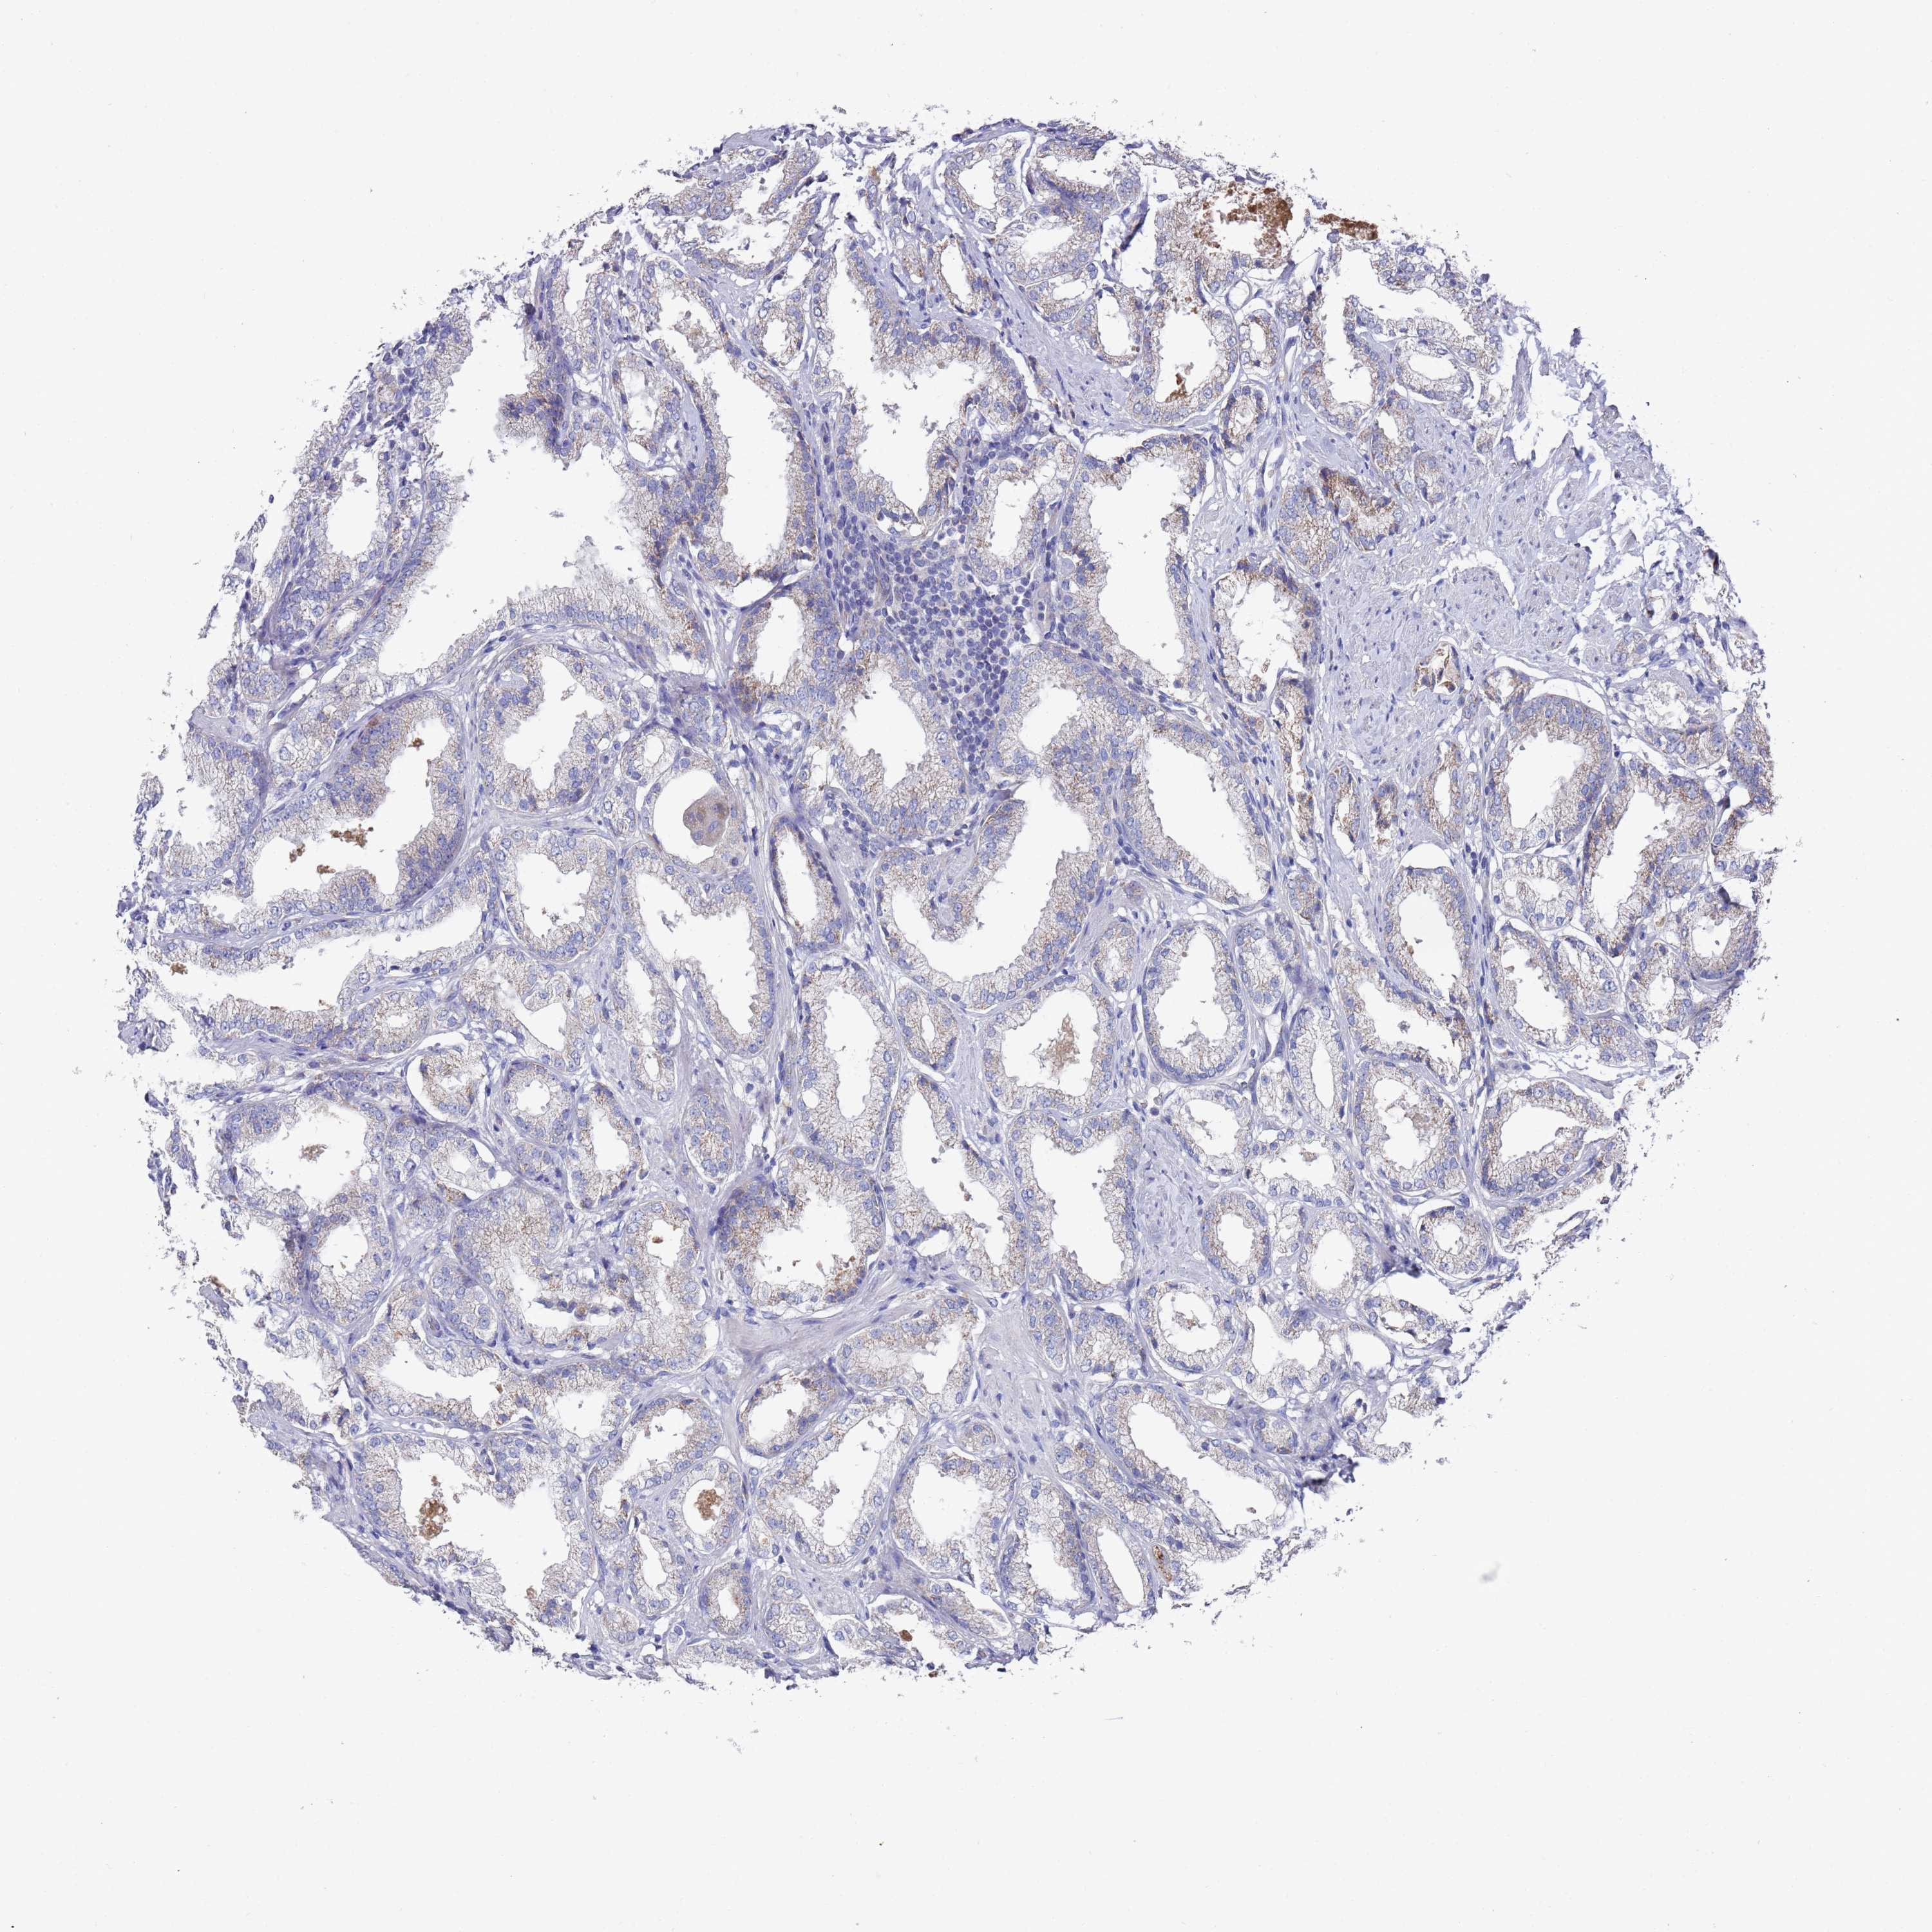

PROSTATE CANCER - Protein expressioni

A mouse-over function shows sample information and annotation data. Click on an image to view it in a full screen mode. Samples can be filtered based on level of antibody staining by selecting one or several of the following categories: high, medium, low and not detected. The assay and annotation is described here.

Note that samples used for immunohistochemistry by the Human Protein Atlas do not correspond to samples in the TCGA dataset.

Antibody stainingi

Antibody staining in the annotated cell types in the current human tissue is reported as not detected, low, medium, or high, based on conventional immunohistochemistry profiling in selected tissues. This score is based on the combination of the staining intensity and fraction of stained cells.

Each image is clickable and will lead to virtual microscopy that enables deeper exploration of all samples and also displays staining intensity scores, fraction scores and subcellular localization as well as patient and tissue information for each sample.

Antibody HPA021453

Antibody HPA045649

Staining

High

Medium

Low

Not detected

Intensity

Strong

Moderate

Weak

Negative

Quantity

>75%

75%-25%

<25%

None

Location

Nuclear

Cytoplasmic/membranous

Cytoplasmic/membranous,nuclear

Adenocarcinoma, NOS

Adenocarcinoma, High grade

Adenocarcinoma, Low grade